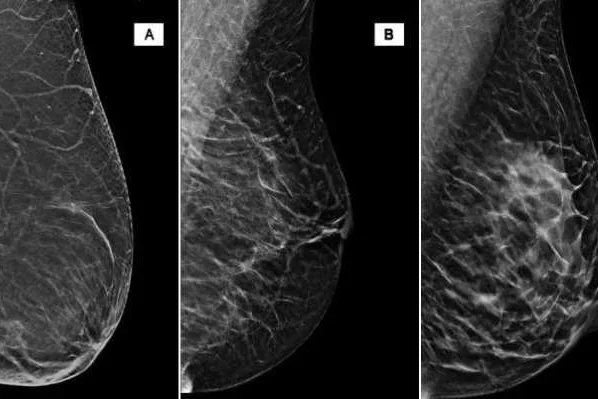

A recent study found that false positive breast biopsies cost the healthcare system over $2 billion per year. According to the National Cancer Institute, mammograms miss about 20% of breast cancers while one in 10 women receive a false positive result. Jamie Yuccas spoke with researchers at Google and UCLA who have developed an artificial intelligence program to help better diagnose mammograms and biopsies.